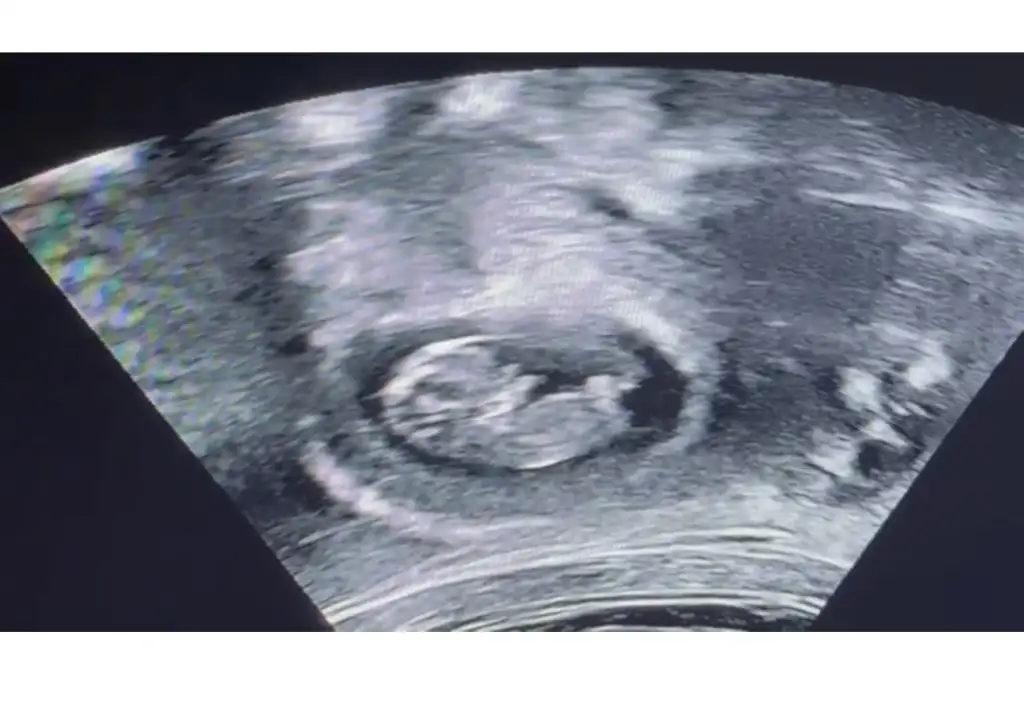

Kız gibi duruyor bence kız olcakKizlar bana da bakar msnzzz

Nerden anlıyorsun cnm nub nuKız gibi duruyor bence kız olcak

İnternetten nub teorisi diye arastır sende tahminde bulunabilirsin :)Nerden anlıyorsun cnm nub nu